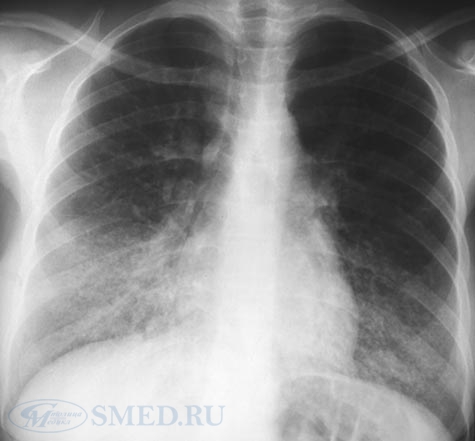

Самым результативным способом выявления болезни легких, является прослушивание новорожденного на присутствие хрипов в области грудной клетки и рентгеновское исследование.

Диагностика пневмонии у новорожденных проводиться с помощью рентгенологических и лабораторных исследований. Кроме того, верная постановка диагноза невозможна без учета клинических симптомов и данных анамнеза. Если у крохи выявлено воспаление легких, нужна госпитализация.

- Сегментарная – данный вид воспаления развивается после ОРВИ или другой вирусной инфекции. Выявить его можно только с помощью рентгеновского снимка, так как симптоматика очень незаметная и поставить диагноз на ее основании невозможно. Выздоровление, как правило, наступает на третью неделю после начала лечения.